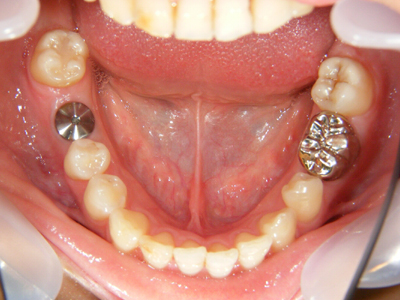

10. インプラント埋入後

インプラントを埋入後、約1ヶ月後の写真です。患者様はインプラントを悩んでいる時期が長かったので、ブラッシングの指導をしっかりさせていただきました。その結果、常に清潔を維持できるようになったので、周囲歯肉の治癒も早かったです。初診時では可愛い女性なのに、歯肉炎で歯肉も真っ赤で辛かったと思います。

12. インプラント歯冠作製前

インプラント体埋入から約3ヶ月後です。しっかりインテグレーション(骨との結合)が得られたので、これから上部構造を作製します。この場合は既成のアバットメントを装着しました。インプラント周囲歯肉も予想以上に健全です。

14. インプラント歯冠セット時下顎面観

右下6番部インプラントにセラミック冠を装着(ほとんどの症例では仮着)した下顎写真です。

15. インプラント歯冠セット時右側面観

右下6番部インプラントにセラミック冠を仮着したところです。何とか歯頚部の連続性が保てました。又歯冠乳頭も少し温存できました。キャンセルが多く苦労しましたが、今後は確実に定期健診を受けて下さらないと保障できませんよ。何かあれば、いつでも相談してください。